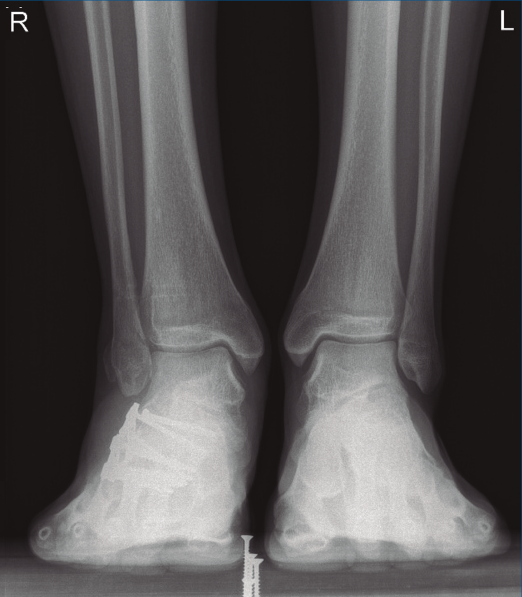

Figura 1. Luxación del astrágalo en mortaja tibioperonea, fractura maléolo peroneo y espacio subperoneo ocupado por calcáneo.

Se trata de un varón de 19 años que ingresa en reanimación tras precipitarse desde una altura de aproximadamente 10 metros. El paciente presenta una fractura estallido de L3 con afectación del canal medular junto con una fractura del vértice inferior de L4, así como una fractura luxación de calcáneo, asociada a una fractura del maléolo peroneo y del maléolo tibial posterior (Figuras 1 a 6) diagnosticadas mediante TC total body (por eso no se dispone de radiografías simples al momento del ingreso). Como podemos comprobar, se trata de una fractura de doble trazo de tipo hundimiento/depresión de la carilla articular (Figuras 5 y 6).

A los 9 meses únicamente presentó dolor ocasional al nivel de la articulación subastragalina y molestias en la planta del pie al deambular descalzo, por lo que se pauta plantilla amortiguadora, con la que mejora notablemente la sintomatología. Presentó una puntuación de 83 sobre 100 en la escala de la American Orthopaedic Foot and Ankle Society (AOFAS), ligeramente superior a la media descrita en estudios previos(2,3). Radiográficamente se evidenció una anatomía restablecida del calcáneo y de la sindesmosis, así como una altura adecuada de ambos tobillos (Figuras 12 y 13). Dada la buena evolución, se decidió continuar con el seguimiento anual del paciente sin realizar la extracción del material de osteosíntesis, para valorar la necesidad de una futura artrodesis sub­astragalina.

Figura 13. Radiografía anteroposterior de ambos tobillos a los 9 meses de la cirugía.